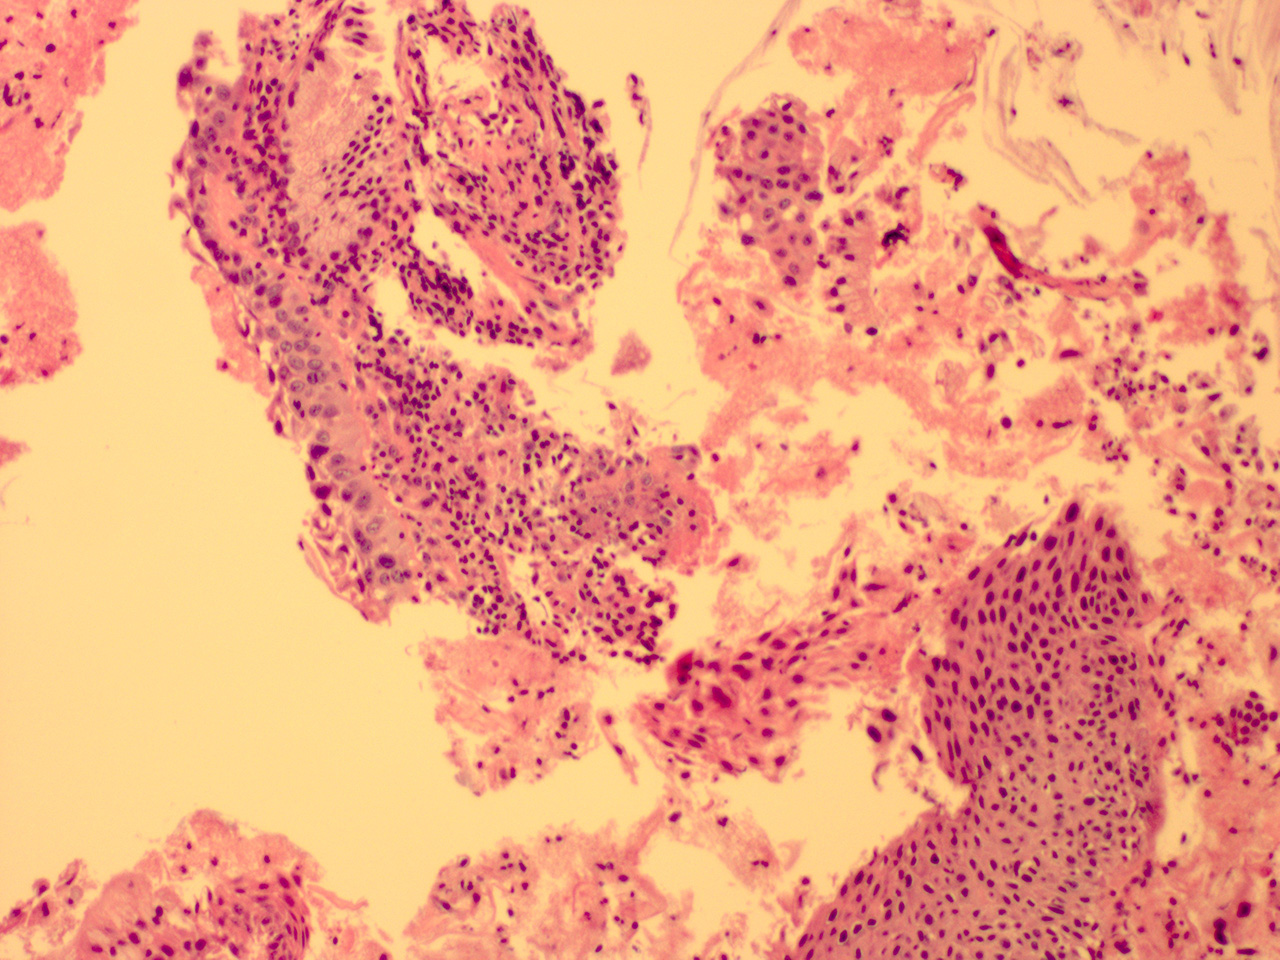

![]() Case 2

Soft Bx CIN 2 10x - Low Power |

Soft Bx CIN 2

40x - High Power